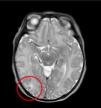

The electroencephalogram revealed bilateral temporal paroxysmal discharges and the brain MRI a discrete hyperintensity in the right posterior temporal subcortical white matter on T2-weighted imaging (Fig. 2).